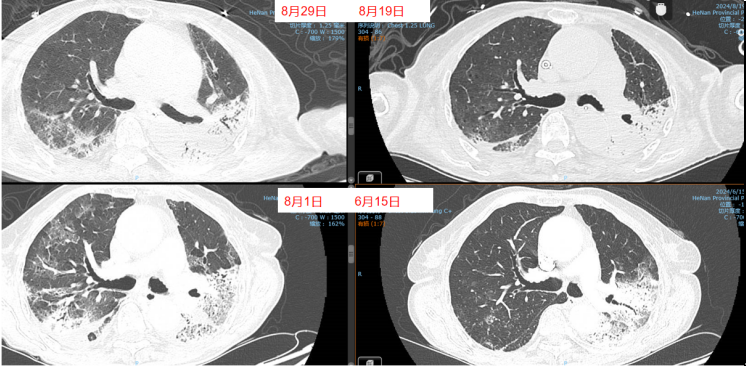

8月11日呼吸机吸氧浓度40%,ECMO气浓度约为80%,持续3天,激素减量氧合恶化,因心脏问题不能俯卧位通气(心率快,应用艾司洛尔及胺碘酮控制心室率)。气道分泌物不多,炎症指标正常。心脏问题,快速性心律失常,请心内科专家会诊,考虑舒张功能障碍,建议盐酸地尔硫卓联合胺碘酮控制心室率,血压低考虑可能血管张力问题,为减轻去甲肾上腺素对心脏的刺激,调整间羟胺维持血压。6月26日用抗肿瘤靶向药物后,8月1日肺部CT,双肺病变明显加重,肿瘤进展还是感染诱发?或是肿瘤靶向药物引起的免疫相关性肺损伤?下一步怎么办?肿瘤靶向药物还能用吗?8月11日请詹庆元教授会诊,考虑肿瘤靶向药物引起间质性肺炎可能性大,甲强龙80 mg q12h;心内科建议倍他乐克6.25 mg q12h口服联合盐酸地尔硫卓控制心室率;间羟胺替换去甲肾上腺素。8月12日心率65~85次/分,俯卧位8小时,白天ECMO 80%下调60%。患者氧合持续好转,随着病情好转,抗生素降阶梯治疗。8月13日,BALF涂片发现大量白细胞,以及多种形态阴性杆菌,像洋葱伯克霍尔德菌和伊丽莎白菌。8月14日,tNGS结果回报按蚊伊丽莎白菌、洋葱伯克霍尔德菌和脓肿分枝杆菌。据此调整抗感染药物:磺胺2片tid,多黏菌素E,美罗培南,利奈唑胺,伏立康唑。8月20日撤离ECMO。8月21日,病原学提示脓肿分枝杆菌进行性增多,加用左氧氟沙星。8月26-28日尝试甲强龙减量(60 mg→40 mg),患者再次再次出现氧合变化,未能成功转换为无创通气,有创通气PS降至8 cmH2O,PEEP 5 cmH2O。复查胸部CT,发现右肺渗出性病变再次出现。8月29-30日,甲强龙剂量调整为80 mg。8月31至9月3日,甲强龙剂量调整为60 mg。8月27日复测tNGS,回报木糖氧化无色杆菌(序列数47605),人类疱疹病毒1型(序列数176998),按蚊伊丽莎白菌、洋葱伯克霍尔德菌和脓肿分枝杆菌序列数较前减少。细菌室回报木糖氧化无色杆菌。患者出现了一些不良反应,包括骨髓抑制,纤维蛋白原、血小板、血红蛋白、白细胞、淋巴细胞数都在降低。考虑可能是磺胺药物和利奈唑胺引起,所以停用这两种药物。调整抗感染药物:阿米卡星雾化,左氧氟沙星,多西环素,伏立康唑,阿昔洛韦。之后由于不良反应,8月31日停用了左氧氟沙星和多西环素。9月3日查血,患者血小板升高。如下图所示,6月15日为抗肿瘤药物使用前,8月1日为抗肿瘤药物使用后,8月19日第一次复查CT,激素减量后,8月29日再次复查CT,右肺渗出性病变较前明显增多(图4)。

图4 患者影像学变化